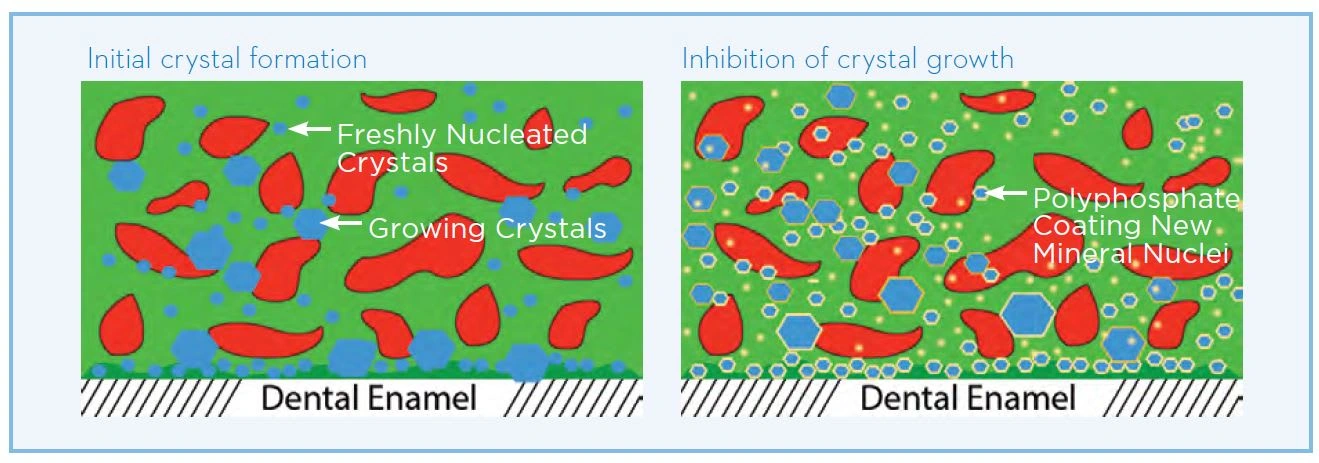

Dental calculus forms through the mineralization of dental plaque, resulting in a variety of different crystalline forms (Sidaway 1978). First, new crystals form, that are composed of calcium and phosphate, which then grow and harden into calculus (Figures 18-19). The mineral content for supragingival and subgingival calculus is on average 37% and 58% by volume, respectively (Friskopp & Isacsson 1984). Supragingival calculus also contains bacterial debris and toxins as well as viable aerobic and anaerobic bacteria (Tan et al. 2004a; Tan et al. 2004b; White et al. 1997). This is of clinical significance as it can be a reservoir of pathogenic bacterial species (Tan et al. 2004b). Dental calculus is common in adults, and less common in children (Anerud et al. 1991).

Figure 18. Formation of dental calculus

Figure 18. Formation of dental calculus

Mechanism of action

Pyrophosphate helps to reduce dental calculus through a mineral chelating effect that inhibits plaque mineralization. It has a natural binding affinity for calcium ions. The anticalculus effect is due to adsorption and binding of the pyrophosphate to the tooth surface and to forming crystals of calcium phosphate in plaque, helping to inhibit the growth and maturation of calculus (White & Gerlach 2000; Rykke & Rolla 1990; Rolla et al. 1988). Sodium hexametaphosphate (Figure 20) is a longer-chain form of pyrophosphate, with more binding sites. It has a greater affinity for hydroxyapatite surfaces, and binds strongly to the tooth surface and the surface of developing calculus in plaque. (Figure 21 White & Gerlach 2000; Baig et al. 2002, Busscher et al. 2002)

Figure 21. Mechanism of action of sodium hexametaphosphate

Figure 21. Mechanism of action of sodium hexametaphosphate